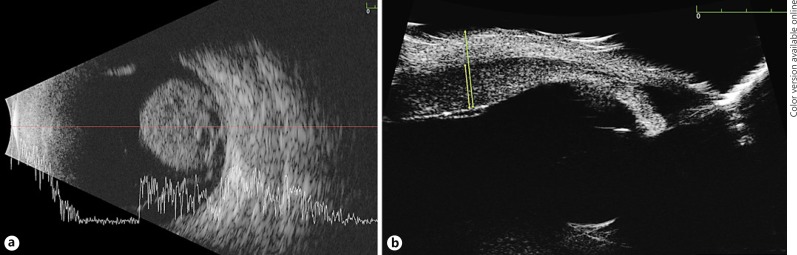

Fig. 2.

B-scan of larger posterior lesion (a) and ultrasonic biomicroscopy of ciliary body lesion (b).

A 52-year-old woman with no prior ocular or medical history presented with complaints of decreased peripheral vision in her left eye. Family history was negative for cancer and the right eye was unremarkable. Best-corrected visual acuity was 20/20 OD and 20/150 OS and intraocular pressure was 14 mm Hg OD and 16 mm Hg OS. There were no signs of episcleral melanocytosis. Fundoscopic exam revealed no choroidal melanocytosis, confirmed with transillumination. A large pigmented mushroom-shaped choroidal melanoma was seen (lesion 1) overhanging the optic nerve nasally and occupying most of the nasal hemisphere (Fig. 1). This lesion measured 10.6 mm in diameter and 11.2 mm in thickness. B-scan ultrasonography using the 10-MHz transducer showed cystic cavities, surrounding subretinal fluid, intravascular pulsations, and no extrascleral extension (Fig. 2). Further ocular examination revealed a 9 × 1.7 mm ciliary choroidal mass superiorly, which was clinically thought to represent a nevus (lesion 2). Ultrasonic biomicroscopy of lesion 2 showed a 1.7-mm lesion extending from the ciliary body and pars plana into the choroid with medium reflectivity and no subretinal fluid, intrinsic vascular pulsations, or extraocular extension. The AJCC classification of tumor 1 was T3a and tumor 2 was T1b.